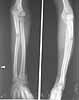

This patient,a middle aged malewas a diagnosed case of hypophosphatemic osteomalacia on treatment. Unfortunately he discontinued treatment since he was poor and also neutral phosphate was not available locally. He presented with pathological fracture of left femur and a failing neck of same femur.

We managed to get neutral phosphate, initiated medical treatment and did an antegrade SIGN nailing of left femur along with couple of screws to neck using miss a nail technique. He complained of pain of the right femur and both forearms. In OT these areas were screened using image intensifier and found that he has looser zones of all these with impending fractures. Yesterday we did a retrograde nailing of right femur usingSIGN nail. Both ulnas were stabilised usingLambrudini wires in a closed fashion. All fractures and looser zones were stabilised by closed surgery using image intensifier. It may be interesting to see the post of picture of both the hips in which one side shows an antegrade femoral SIGN nail and the other side shows a retrograde SIGN nail.